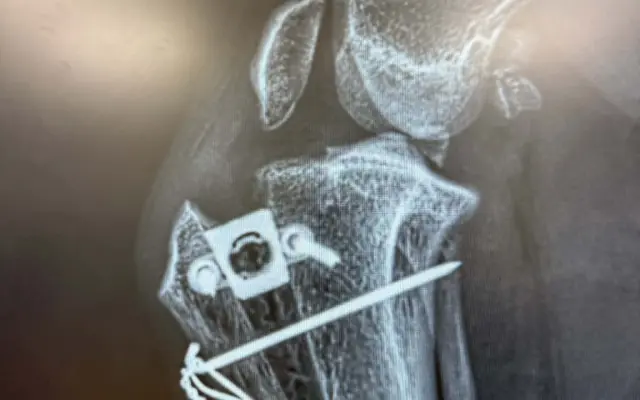

Pomoc pro Kiru – druhá operace přetrženého vazu během pár měsíců

Nešťastný příběh Kiry